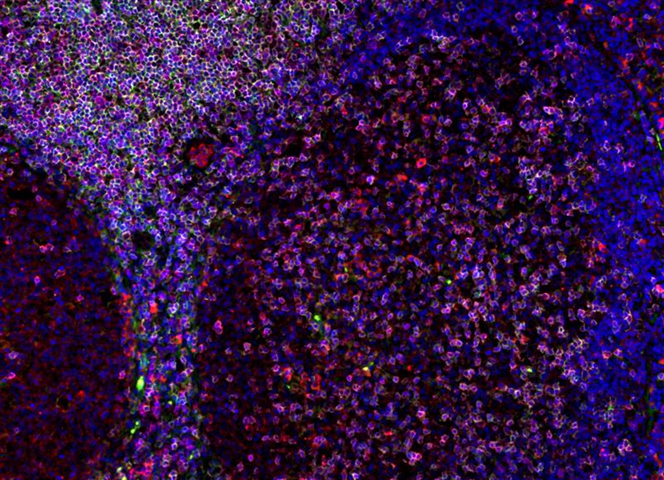

Immunofluorescence staining in FFPE human tonsil of CD3 (magenta), CD4 (green), and PDL1 (red).